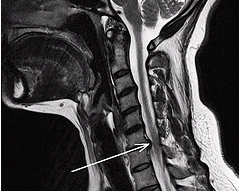

교모세포종(Glioblastoma)

- 증상

-

뇌전증 발작 ,

구토,

두통,

오심

- 관련질환

원발성 중추신경계 림프종,

뇌신경 인플레 ,

신경모세포종,

양성 뇌종양,

뇌종양,

수두증

- 진료과

종양내과,

방사선종양학과,

소아청소년종양혈액과,

신경외과,

소아신경외과